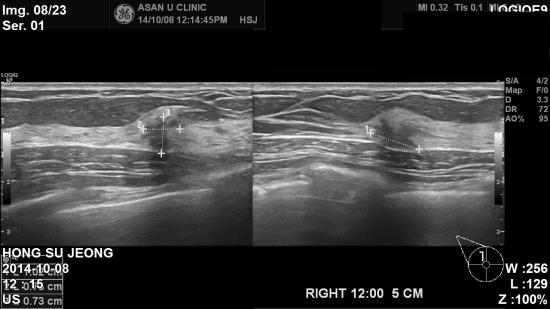

본원 초음파 검사상 우측 겨드랑이 림프절 비대 소견 및

우측 유방 12시 방향에 1.03cm 결절 소견 있어

조직검사

시행하였습니다.

조직검사 결과 상 우측 침윤성 유관암 및 겨드랑이 전이로 진단 되었습니다.